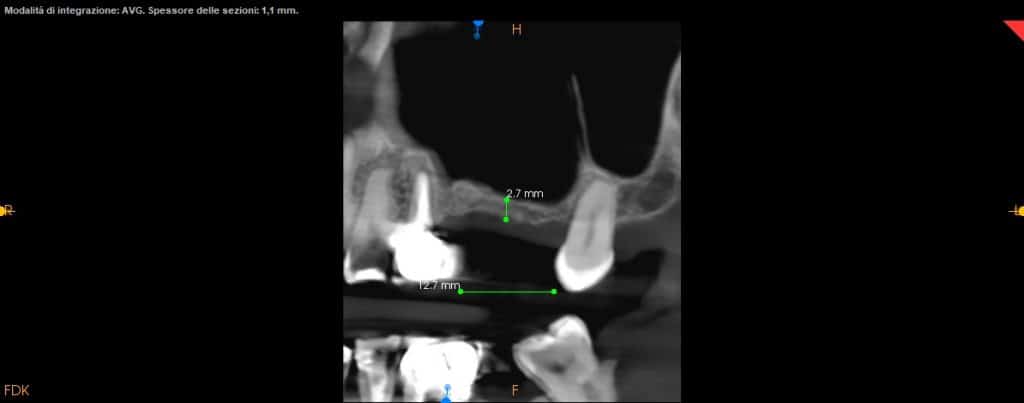

- CBCT helps us for the exact position of the window

- CBCT should guide the detachment of the sinus membrane

- Attention should be paid to any bone septa highlighted by the CT scan

- Two implants are placed drilling the 3 mm of residual crestal bone

CBCT

axial view